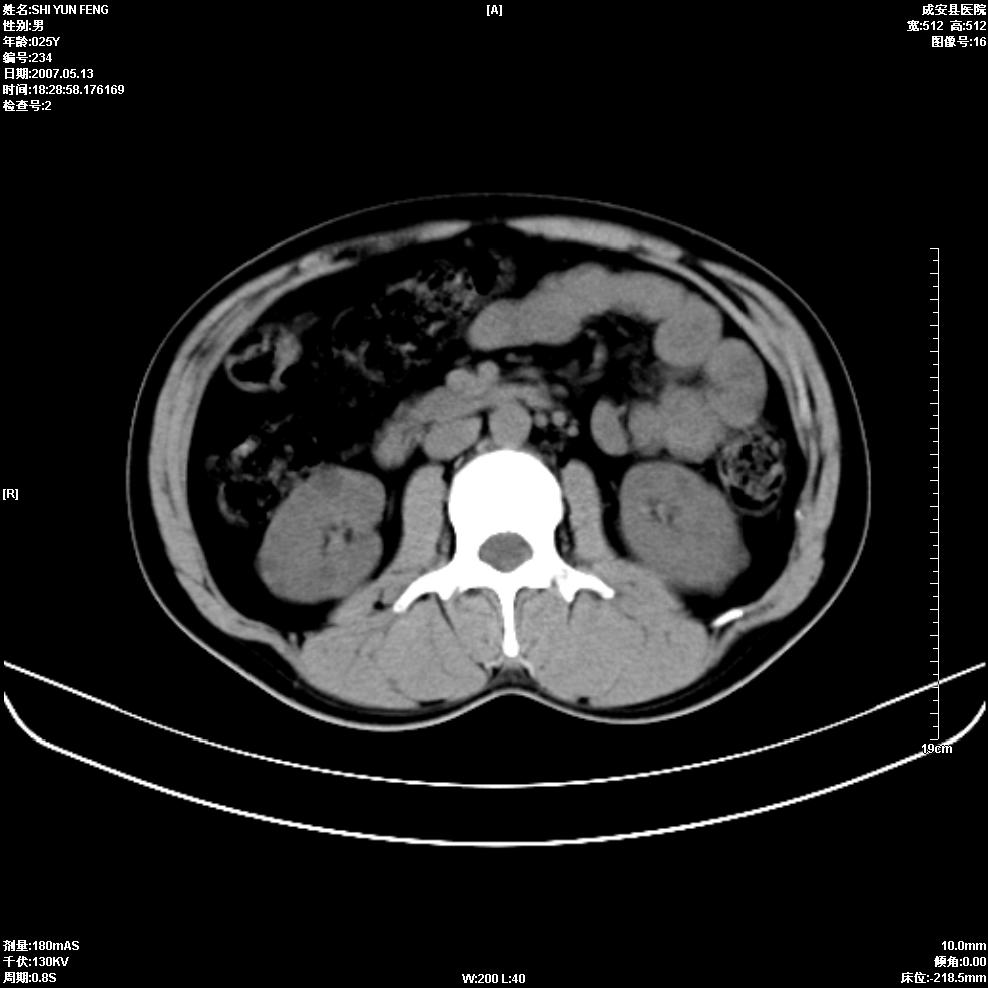

以下是引用zhangzhongshou在2007-5-16 7:36:00的发言:[br]多发性肾囊肿,左肾多发结石。不是多囊肾,楼主箭头所指多考虑左肾囊肿内结石或钙乳,髓质海绵肾不完全除外。[br][br][本贴已被 zhangzhongshou 于 2007-5-16 7:37:18 修改过][br][br][本贴已被 zhangzhongshou 于 2007-5-16 18:15:09 修改过]